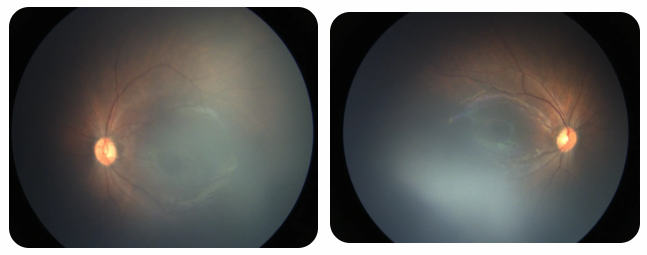

廈門眼科中心黎曉新名醫(yī)工作室曾接診一名31周出生的早產兒,出生體重僅1300克。由于家長缺乏篩查意識,直到孩子5個月大時眼睛仍不會追光,才前來就診。檢查發(fā)現,患兒ROP已進展至4B期,因纖維血管增殖牽拉導致視網膜脫離,錯過了最佳治療窗口。盡管黎曉新教授團隊成功實施了玻璃體切割手術,孩子的視力仍存在不可逆損傷。此后,孩子開啟了長期隨診復查、治療的“護眼征程”,目前其右眼矯正視力為0.6,左眼為0.8。

近期術前檢查:

早產兒視網膜病變

術后復查:

相比之下,另一位早產寶寶在出生5周后,生命體征穩(wěn)定之時,便在產科醫(yī)生的建議下轉診至廈門眼科中心。經篩查確診為Ⅲ期ROP,黎曉新教授團隊及時為其進行了激光治療。半年后復查顯示,寶寶的視網膜血管發(fā)育正常,視力發(fā)育與足月兒童無異。